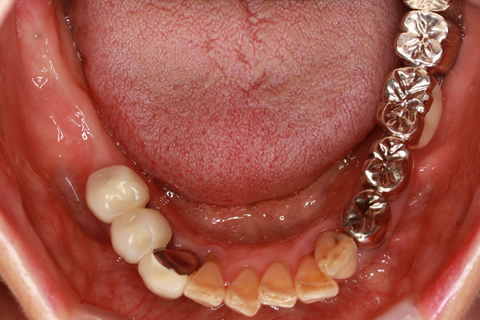

症例2

治療前

インプラント埋入時

治療後

- 年齢・性別

- 57歳男性

- 治療期間

- 3ヶ月

- 抜歯

- なし

- 治療費

- 154万円

- 備考

- 左上5.6.7 及び左下6.7欠損

- 治療内容

- 左上5.6.7と左下6.7欠損部にインプラント埋入

- 施術の副作用(リスク)

- オペによる知覚障害。インプラントによる歯肉炎。インプラント脱落。